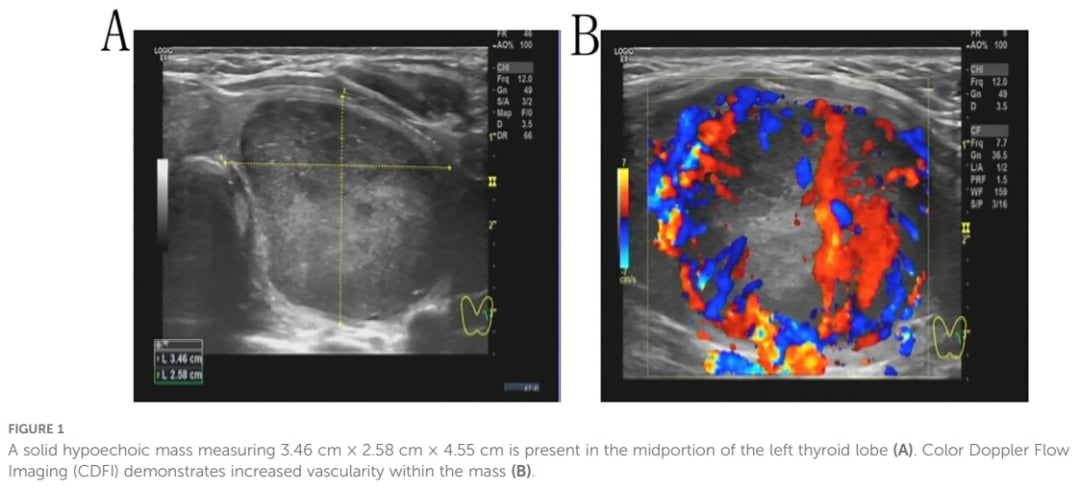

一位43岁的女性患者因发现颈部肿块两个月而就医。超声检查显示其左侧甲状腺叶中部有一个3.46×2.58×4.55 cm的实性低回声肿块,血流丰富,超声诊断为TI-RADS 4A类结节。初步的细针穿刺活检(FNAB)提示可能为炎性增生性病变。

▲图1 左甲状腺叶中部可见一实性低回声肿块